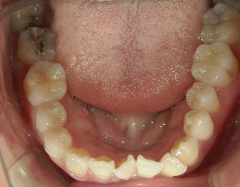

矯正_灰色.pngno.37_7548_治療前_上.JPG矯正_灰色.png

矯正_灰色.pngno.37_7548_治療前_下.JPG矯正_灰色.png